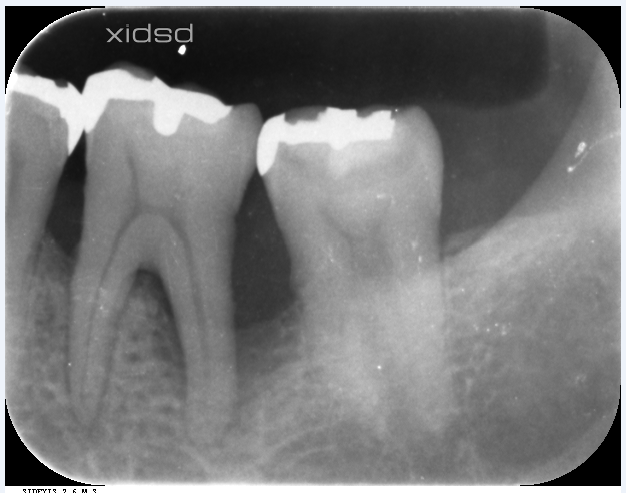

再生が見られ、ポケットが安定致しました!!

神経も歯も抜かない

体に優しい治療です。